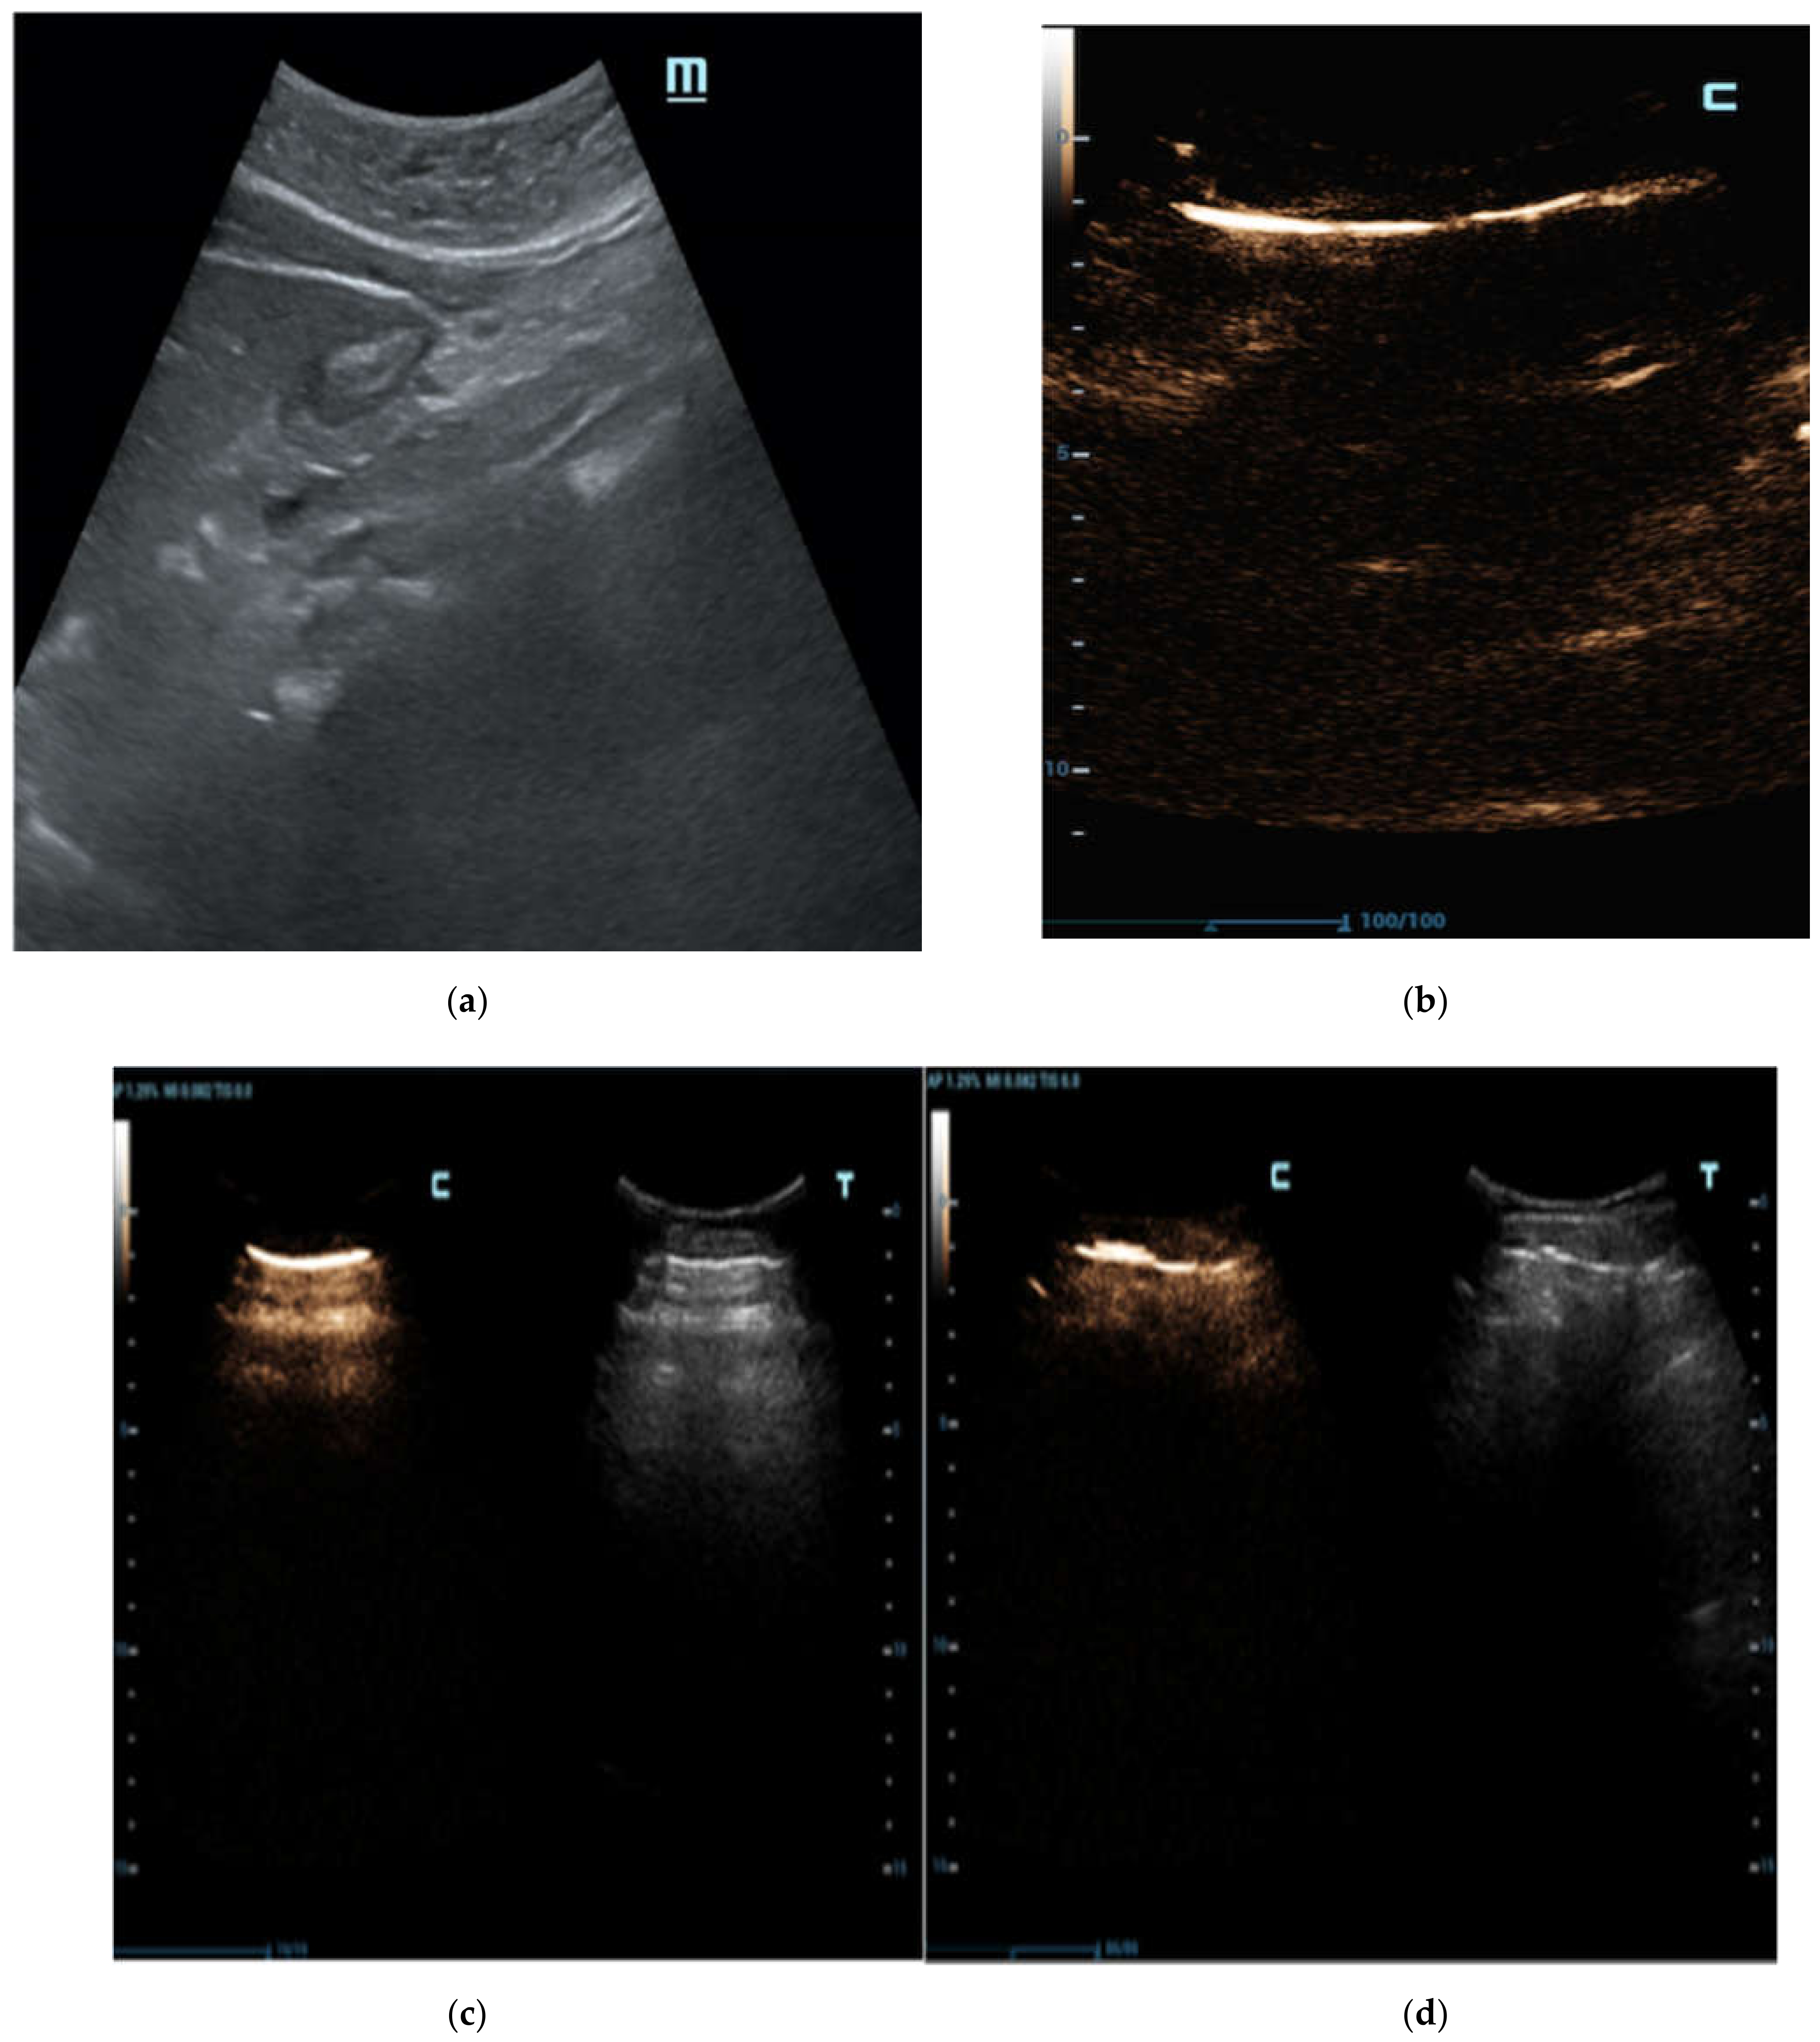

In our patients, larger air bubbles appeared as bright, highly echogenic lines with distal reverberation and shadowing artifacts, as ring-down or comet-tail artifacts on B-mode

(

Figure 2a); free air can also be detected beneath the anterior abdominal wall, where it generally accumulates in the supine patient (

Figure 2b).

C-mode gave a more intense appearance to the peritoneal stripe when compared to B-mode, identifying the amount of free air, similar to the strongly enhanced peritoneal lines in the pre-hepatic space (

Figure 3), and better enounced the presence of intensely enhanced small amounts of air around the falciform ligament (

Figure 4a), as confirmed by the CT scan (

Figure 4b).

Therefore, in some cases of our study population, a small amount of air under the abdominal wall was not clearly visible, and was potentially lost when the examination was not performed in expert hands, where it was misunderstood as a simple anatomic interface on B-mode (

Figure 5a,b). In these cases, C-mode demonstrated its ability to distinctly reveal highlighted peritoneal stripes (

Figure 5c) that modified their aspects as the patient’s position changed (

Figure 5d).